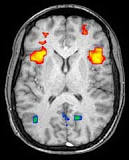

Neuroimaging falls into two broad categories:

- Structural imaging, which is used to quantify brain structure using e,g, voxel based morphometry.

- Functional imaging, which is used to study brain function, often using fMRI and other techniques such as PET and MEG (see below).